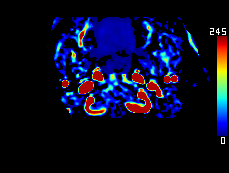

Perfusion MRI를 이용한 측부혈류영상

조기정맥기까지 남은 허혈 영역 : 초기 뇌경색 영역과 일치 (일치율 0.97)

모세혈관기의 허혈 영역 : 허혈반음영을 반영 (일치율 0.89)

European Radiology 2024;34(3):1411-1421 The Collateral Map, Radiologia Medica 2025;130(2):235-247 The CT Collateral Map